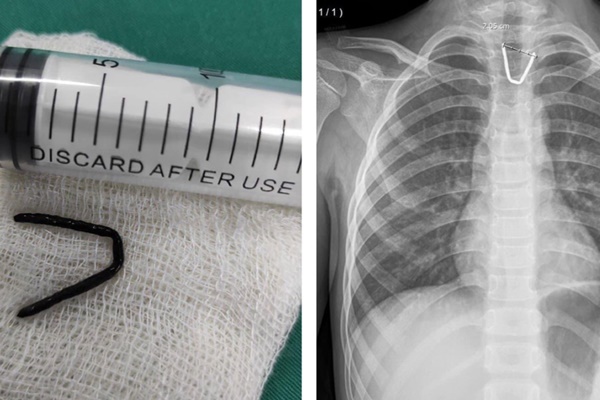

Các bác sỹ đã mất khoảng 2 tiếng đồng hồ để lấy lần lượt từng cây kim ra. “Việc đưa 8 cây kim ra ngoài là điều rất khó khăn, nhưng chúng tôi đã làm được điều đó với sự hỗ trợ của Chúa. Chúng tôi thậm chí còn cố gắng lấy được những chiếc kim ở vị trí nguy hiểm”, bác sỹ phẫu thuật Efrain Salazar Tito nói..